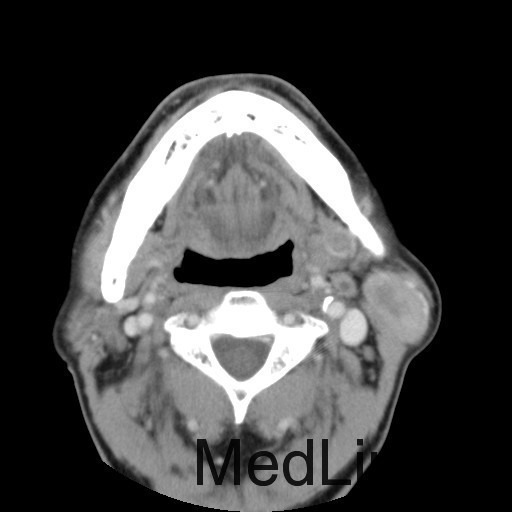

患者:男,64岁。 主诉:左耳垂下肿物1年余 病史:患者1年余前发现左耳垂下肿物,逐渐增大,与进食无关,无疼痛、麻木感,未予治疗。 体查:左右颜面部基本对称,双侧上、下颌骨未及明显异常膨隆,左耳垂下腮腺区见一膨隆肿物,大小约为4cm×3cm,边界欠清,质软,表面皮肤无红肿、破溃、出血,无触痛,皮温正常,活动度可。 辅助检查:无

诊断:左腮腺肿物(?) 治疗:入院后上颌CT平扫+增强:左侧腮腺深叶结节灶,考虑良性病变,腺淋巴瘤与多形性腺瘤鉴别,排除手术禁忌症,于2015-10-16送手术室全麻下行"左腮腺深叶肿物切除+面神经解剖+邻近皮瓣转移修复术"。术后病理提示:左腮腺肿物,符合多形性腺瘤。